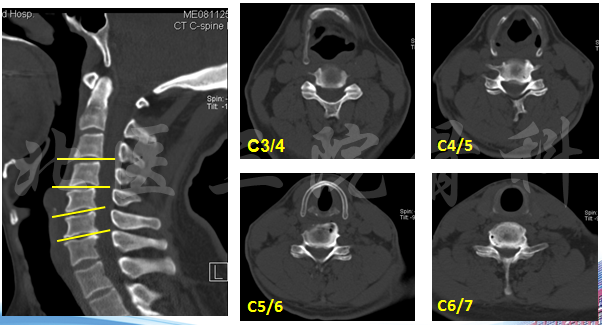

影像学检查

CT

诊断:脊髓型颈椎病;颈椎间盘突出 (C3-C6);发育性颈椎管狭窄。